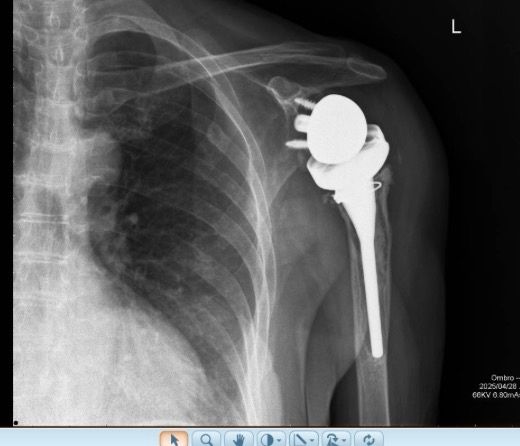

Segundo caso de utilização do sistema VIP Arthrex numa revisão de prótese invertida por loosening asséptico secundário a notching inferior.

Planeamento pre operatório após remoção de implantes anteriores. O sistema permite remover implantes e simular várias opções de dimensão e posicionamento quer da baseplate e glenosfera bem como do componente úmeral. Obtivemos um resultado em termos de mobilidade passiva no intra operatório exatamente igual ao planeado. Trata-se de uma inovação incrível na cirurgia de precisão, útil sobretudo em revisões complexas. O grupo do ombro da Luz Oeiras a inovar mais uma vez.